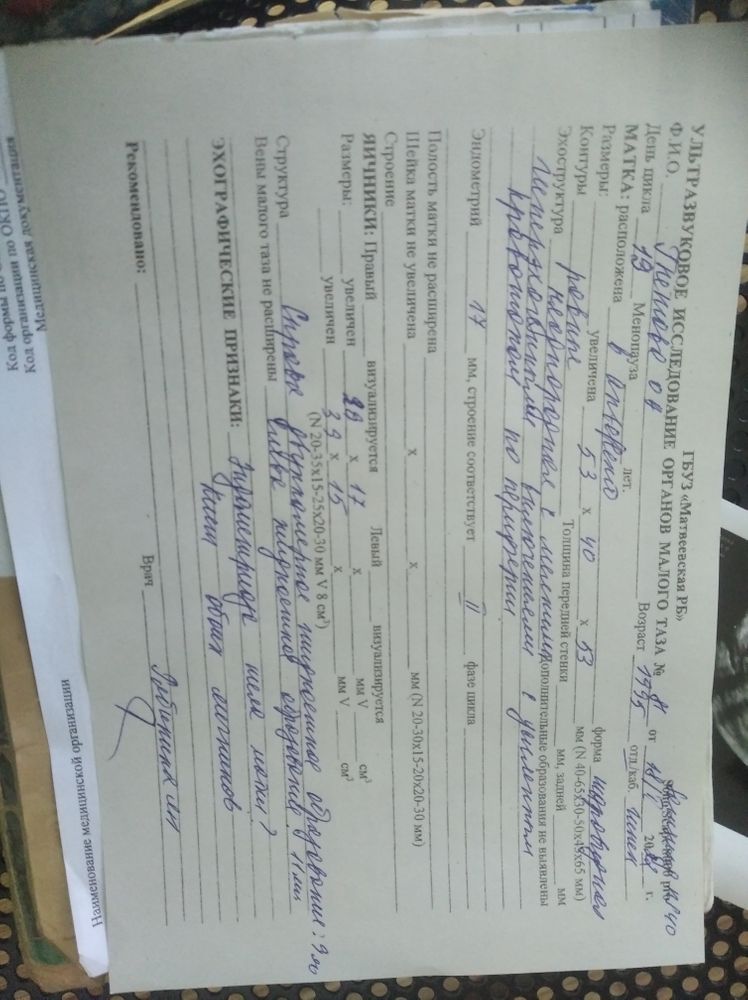

УЗИ показывает беременность 3-4 недели а тест отрицательный

Была сегодня у врача, боль в левом боку. Я кормлю грудью, ребенку 8 месяцев. Месячные пришли только вот 31 декабря и 5 января закончились. Раньше не было с самих родов. Сказали что возможно беременность 4-6 недель, видно пузырик на УЗИ. Сказали сделать тест, сделала он отрицательный. Что же это тогда может быть, может кто то сталкивался с таким.

По узи пишут только кисты обоих яичников и подозрение на эндометриоз.Из-за кист могут быть боли и задержка

Узист увидела вот это и говорит что скорее всего беременность. Что тогда может быть если не беременность, что за пузырик. В результате УЗИ не написали но так сказали.

Посмотрела результаты УЗИ ,там не указано,что есть беременность,а прописано эндометриоз и 2 кисты